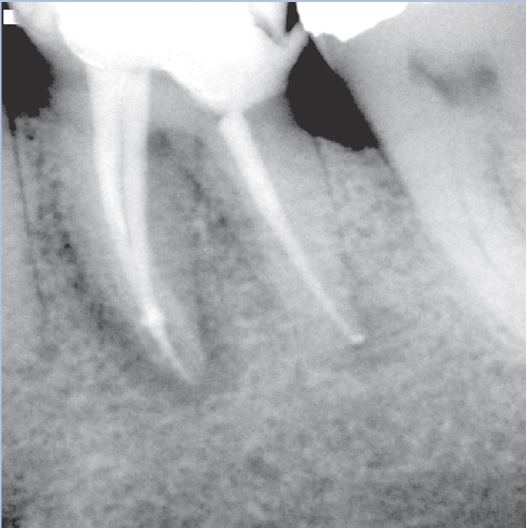

Before

Before Root Canal treatment